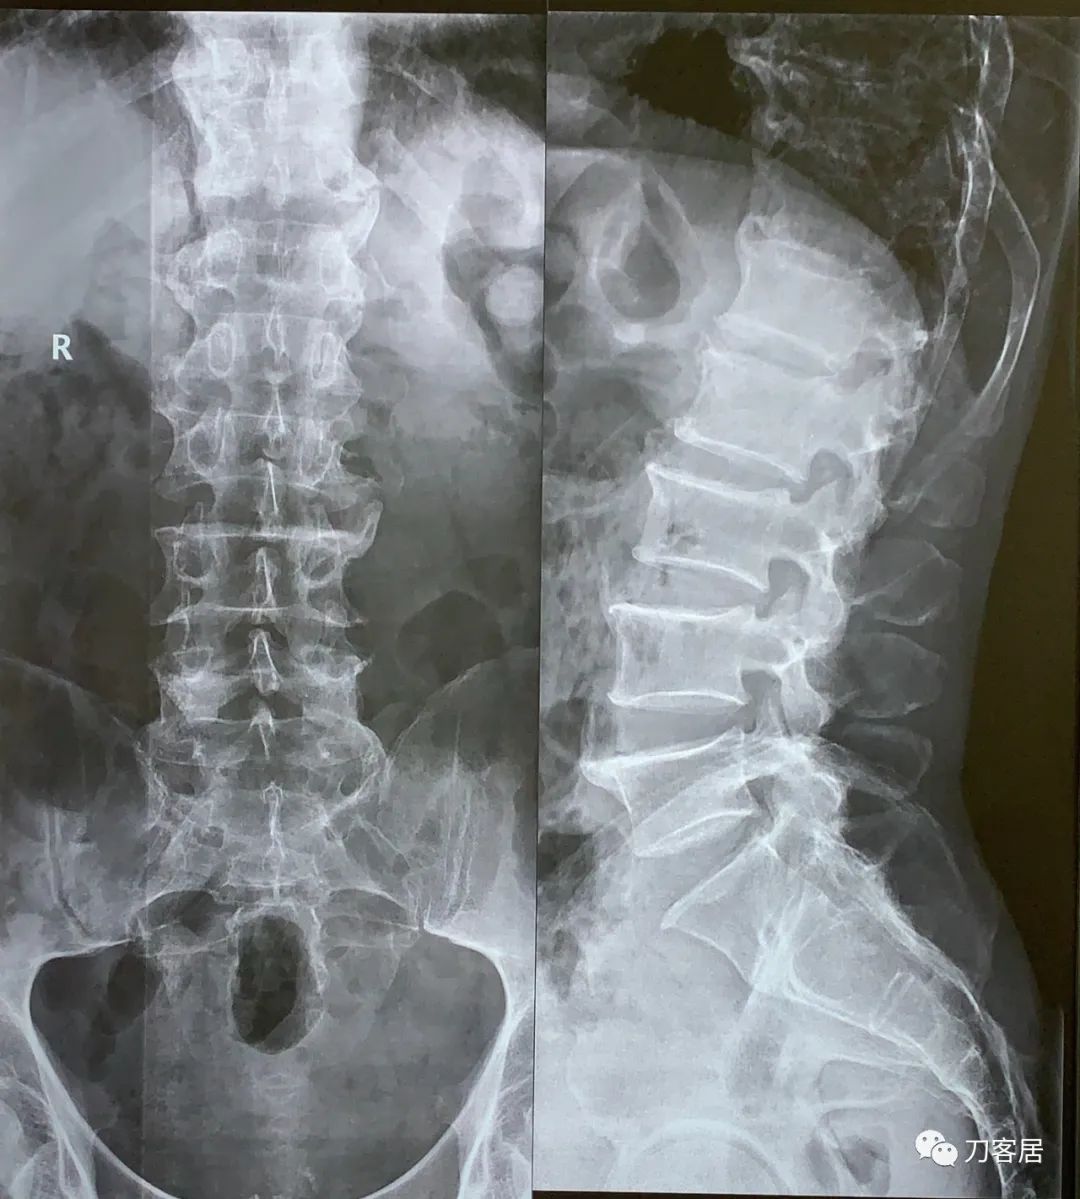

图1. 20210621西京医院腰椎正侧位X线片